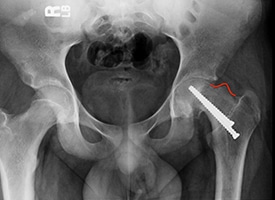

PRE OP

The red line demonstrates a large residual CAM deformity after in situ screw fixation of Slipped Capital Femoral Epiphysis (SCFE). This deformity limits range of motion and impinges against the hip socket causing damage to the joint.

POST OP

The red line demonstrates re-contouring of the femoral neck after arthroscopic treatment. This treatment increases range of motion and prevents further damage to the hip.